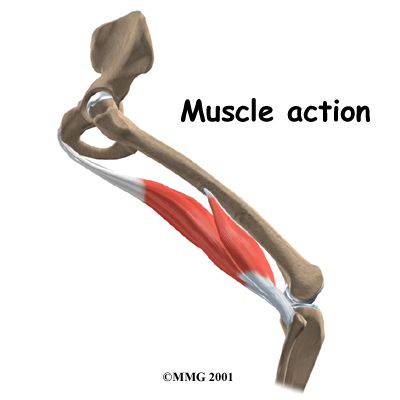

The hamstrings function by pulling the leg backward and by propelling the body forward while walking or running. This is called hip extension. The hamstrings also bend the knees, a motion called knee flexion.

Most hamstring injuries occur in the musculotendinous complex. This is the area where the muscles and tendons join. (Tendons are bands of tissue that connect muscles to bones.) The hamstring has a large musculotendinous complex, which partly explains why hamstring injuries are so common.